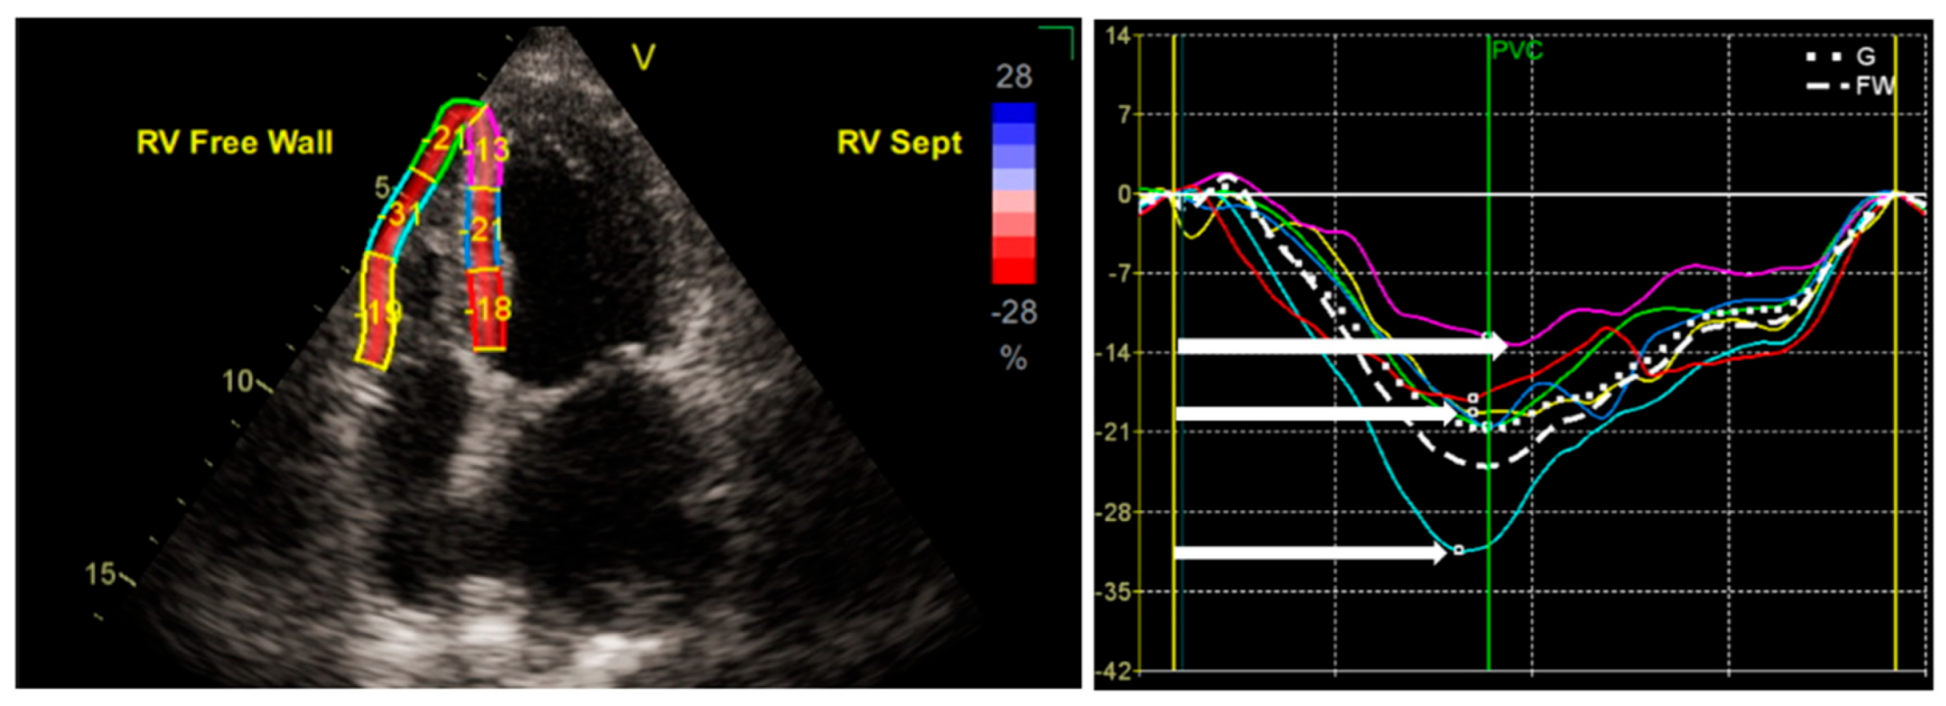

2.3. Speckle-Tracking Echocardiography: A Sensitive Index of RV Systolic Function

- Muraru, D.; Haugaa, K.; Donal, E.; Stankovic, I.; Voigt, J.U.; E Petersen, S.; A Popescu, B.; Marwick, T. Right ventricular longitudinal strain in the clinical routine: A state-of-the-art review. Eur. Heart J. Cardiovasc. Imaging 2022, 23, 898–912. [Google Scholar] [CrossRef]

- Lee, J.H.; Park, J.H. Strain Analysis of the Right Ventricle Using Two-dimensional Echocardiography. J. Cardiovasc. Imaging 2018, 26, 111–124. [Google Scholar] [CrossRef]